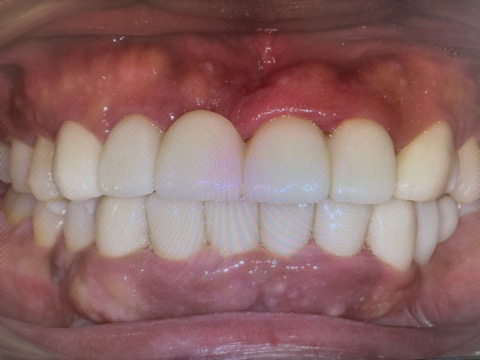

その後、挙上量はシーラシステムを利用して計測し、本来のかみ合わせの位置を再現出来るように技工士さんと相談して本歯を作ってもらいました。

前歯ももちろん審美的に整えて、治療期間は1.5ヶ月でした。

経営者の方はご来院日がたくさん取れないので、1回の治療に長時間かけて、なるべくお仕事に支障がないようにさせていただきながら、早期治療完成を目指しました。

患者様のご理解もあって治療はスムーズに進み、仕上がりにも大変満足していただきました。